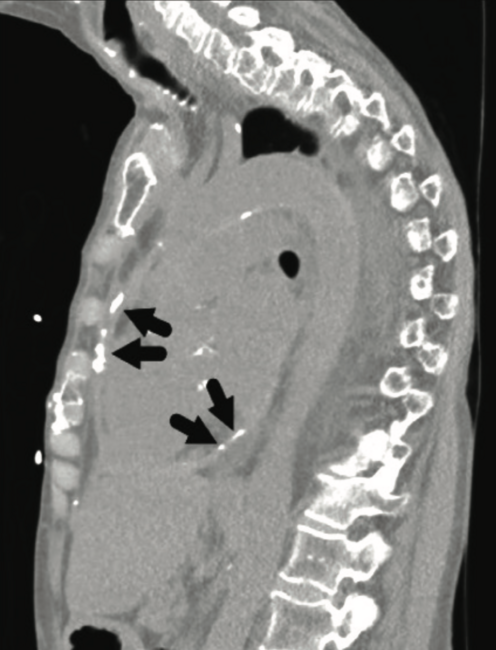

Constrictive pericarditis is a morbid condition, with a challenging diagnosis. Because constrictive pericarditis is generally considered a treatable cause of heart failure, evaluating for and distinguishing constrictive pericarditis from other causes of heart failure is key. This image vignette demonstrates a multimodality approach in the diagnosis of constrictive pericarditis, with emphasis on invasive hemodynamic assessment.